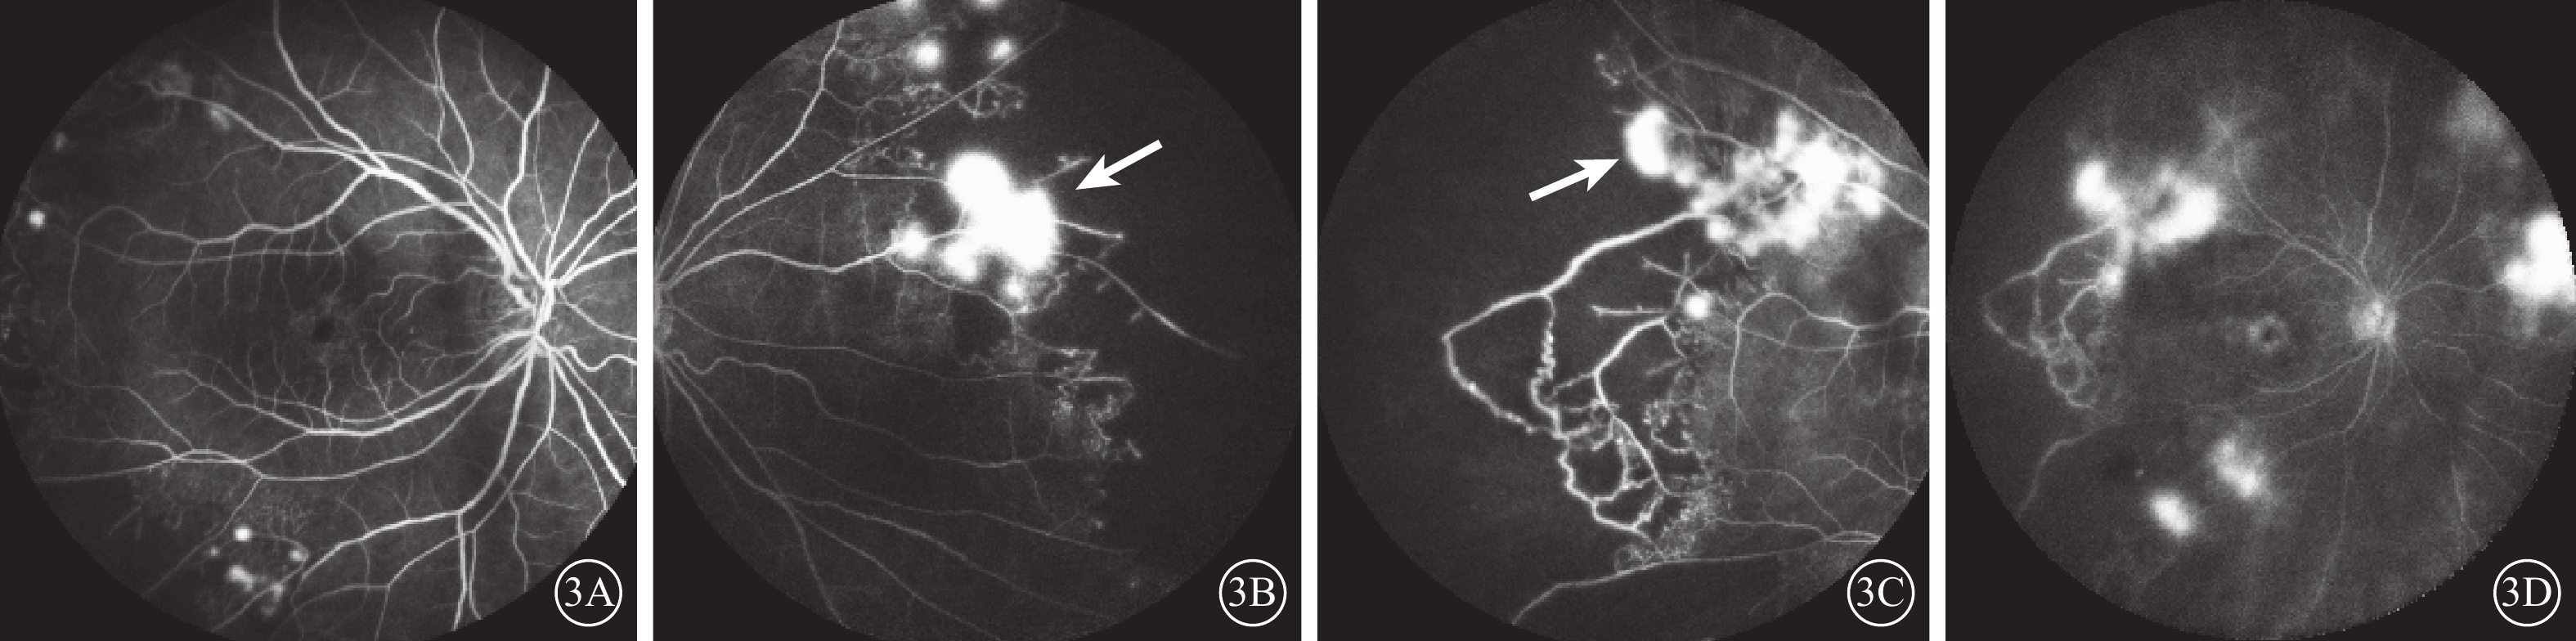

FFA檢查,視網膜血管不同程度熒光素滲漏,以視網膜靜脈和毛細血管滲漏為主,未累及動脈。其中,彌漫性視網膜血管炎5只眼(22.7%,5/22),視網膜靜脈及毛細血管均受累;部分視網膜靜脈受累17只眼(77.3%,17/22),以周邊視網膜血管受累為主,累及多支血管和象限。周邊閉塞性視網膜血管炎16只眼(72.7%,16/22),周邊視網膜大片毛細血管無灌注區,其中視網膜新生血管(圖3)4只眼(18.2%,4/22)。繼發視網膜分支靜脈阻塞3只眼(13.6%,3/22)。合并黃斑水腫10只眼(45.5%,10/22),表現為晚期黃斑區強熒光素積存。

本研究結果顯示,擬診的結核性視網膜血管炎FFA最常見表現是周邊閉塞性視網膜血管炎,此與曹緒勝等[6]研究結果一致。本組22只眼中,72.7%的患眼(16/22)FFA表現為累及靜脈或毛細血管的周邊閉塞性視網膜血管炎,受累區域亦可見大片無灌注區或視網膜新生血管。一項結核性視網膜血管炎的國際多中心大樣本研究中,高加索人種更多表現為非閉塞性視網膜血管炎(71.8%),而亞洲人種更多表現為閉塞性視網膜血管炎(61.1%)[7],這種表現可能是人種與種族的差異。這一結果也與本研究結果一致。此外,由于本病的視網膜血管改變多發生在周邊部,可表現為周邊視網膜的血管滲漏、無灌注區、新生血管形成等,廣角FFA獲取的眼底范圍更大,能發現更多周邊視網膜病變,幫助結核性視網膜血管炎的診斷及治療[8]。本研究中102°廣角FFA共發現17只眼(77.3%,17/22)周邊視網膜病變,而55°FFA僅發現7只眼(31.8%,7/22)周邊視網膜病變,提示臨床對于擬診的視網膜血管炎患者,建議行廣角FFA檢查,能幫助我們識別周邊視網膜病變、改變葡萄膜炎分類,甚至影響治療方案。